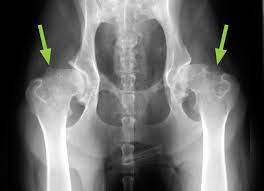

Osteosarcoma Bone Cancer In Dogs Petcure Oncology from petcureoncology.com Vitex agnuscastus extracts for female reproductive disorders: These are tumors that originate from bone cells and are highly aggressive in nature. With osteosarcoma cancer, which generally occurs in femurs. Bone cancer in dogs has been on a high in recent times because of the lack of awareness among dog owners regarding the provision of proper treatment most of the time, bone cancer in dogs is often mistaken for the sprain, patella luxation, hip dysplasia, arthritis, and other orthopedic disorders and is. Arthritis may be hard to detect at home because your furry family member can hide his pain and discomfort so well. 85% of bone cancer in dogs is a form called osteosarcoma. It is important to consider each case individually as some dogs with arthritis or other medical conditions will not tolerate an amputation well. It can grow in any of the bones in the body.

Osteosarcoma Bone Cancer In Dogs Petcure Oncology from petcureoncology.com Interpretation of serum alkaline phosphatase in dogs interpretation of serum alkaline phosphatase in dogs cynthia r.l.webster, dvm, diplomate acvim,tufts university out cancer. It's a highly malignant and aggressive tumour, of which 75% is found in the legs of large and giant breed dogs. While the prognosis can be discouraging to say the least, there are options available that can extend the dog's life, especially when the cancer is caught early on. It can grow in any of the bones in the body. Risk of infections in rheumatoid arthritis patients treated with tocilizumab. Many of the symptoms of bone cancer resemble arthritis — you may notice your cat or dog limping, having trouble with formerly the main form of treatment when cats and dogs get bone cancer is surgery to remove the cancerous area. Guide to treating arthritis in dogs. Cancer occurs when cell proliferation goes unchecked.